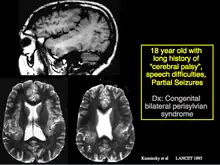

He was one of the first to recognize and prove that mesial temporal sclerosis, a common cause for difficulty in controlling temporal lobe epilepsy, can be identified with MRI scans. He also described the Kuzniecky Syndrome in 1991, also known as perisylvian polymicrogyria. The syndrome is characterized by seizures, cognitive abnormalities, and a peculiar inability to use the mouth and tongue muscles. This syndrome is recognized by as a specific malformation of the brain.

Kuzniecky described the Kuzniecky Syndrome in 1991, also known as perisylvian polymicrogyria.[6] The syndrome is characterized by seizures, cognitive abnormalities, and a peculiar inability to use the mouth and tongue muscles. This syndrome is recognized by as a specific malformation of the brain.[7]